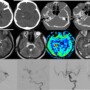

•Axial CT image (a, b) shows hyperdense structures with calcification in the right ambient cistern, bone reformats (c, d) shows hypoplasia and malformed right carotid canal. Calcifications were seen in the shrunken right globe. •Axial T2 weighted images (e, f) shows multilobulated T2 hypointense structures in the right ambient cistern with absence of right ICA flow void. There is right phthisis bulbi. ASL image (g) shows spin trapping in these structures. Post contrast T1 MPRAGE (h) shows lobulated enhancing vessels •DSA image (i, j) reveals ectatic dilated right P1 with multilobulated aneurysmal appearance. There is reformation of the right ACA and MCA from the contralateral circulation through the ACOM. Right PCOM is not visualized ( image k). There is occlusion of right ICA (image l)

Dolichoectasia of right PCA with right ICA occlusion

•Dolichoectasia of the PCA is rarity and is usually postulated to be developmental/ acquired at birth, in contrast to the commoner vertebro-basilar dolichoectasia which is essentially atherosclerotic 1